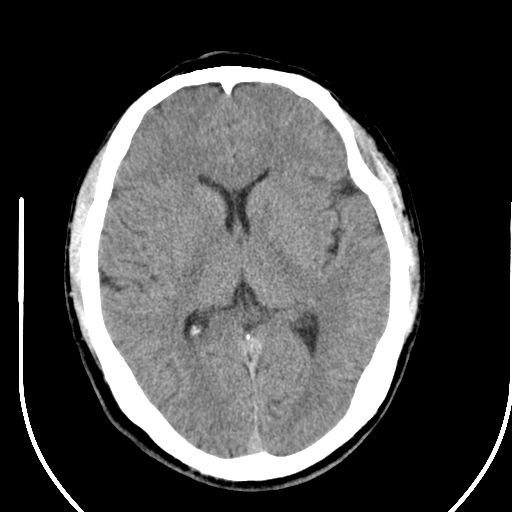

标题: CT25423:头部外伤意外发现右顶叶??? [打印本页]

标题: CT25423:头部外伤意外发现右顶叶???

ct值约13hu。

边缘清晰,没有占位效应,不像脑沟,结合ct值,软化灶可能吧

与脑沟没关系,小软化灶或陈旧性感染吧!

看样年纪不小了直接报腔梗,当然你要想报软化灶也是一样的

考虑右侧额叶巨腔隙灶;建议必要时行mri检查。